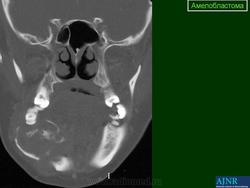

Амелобластома - доброкачественная одонтогенная эпителиальная опухоль, способная к инвазивному росту. Развивается внутри кости, по микроструктуре напоминает стадии развития эмалевого органа, наблюдается чаще у лиц среднего возраста, в 80% случаев поражает тело нижней челюсти в области моляров и премоляров, а также угол и ветвь нижней челюсти. Редко она обнаруживается в области резцов. Проявляется чаще в возрасте 20-50 лет с одинаковой частотой у лиц обоего полу, может встречаться и у детей.

Амелобластома

ID: 3992 Ameloblastoma - maxillary Dr Frank Gaillard - 7 Jul 2008 CT through the maxilla obtained with contrast demonstrates a cystic lesi...

• коронарный